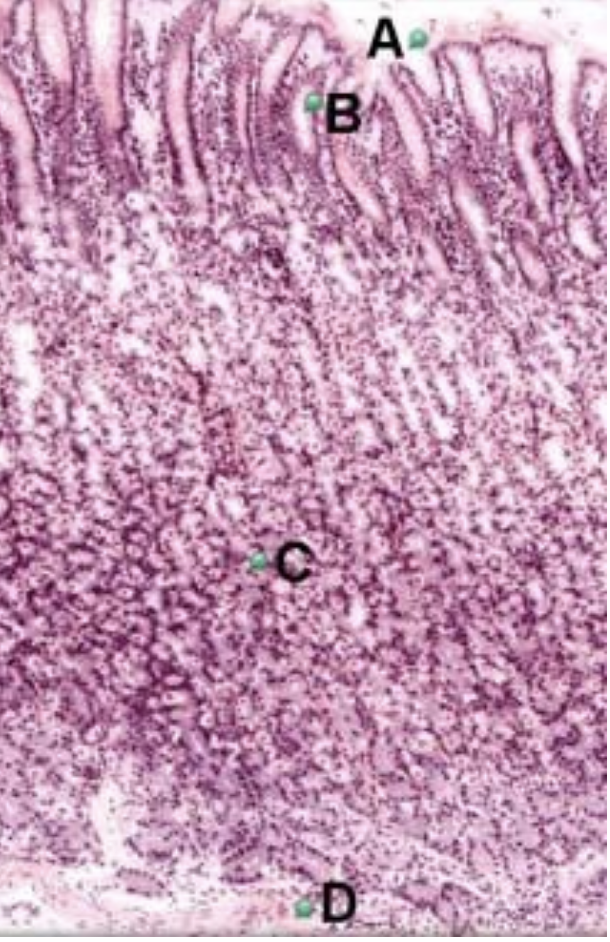

Part A?

opening of gastric pit

Part B?

gastric pit

Part C?

gastric gland

Part D?

muscularis mucosae of stomach